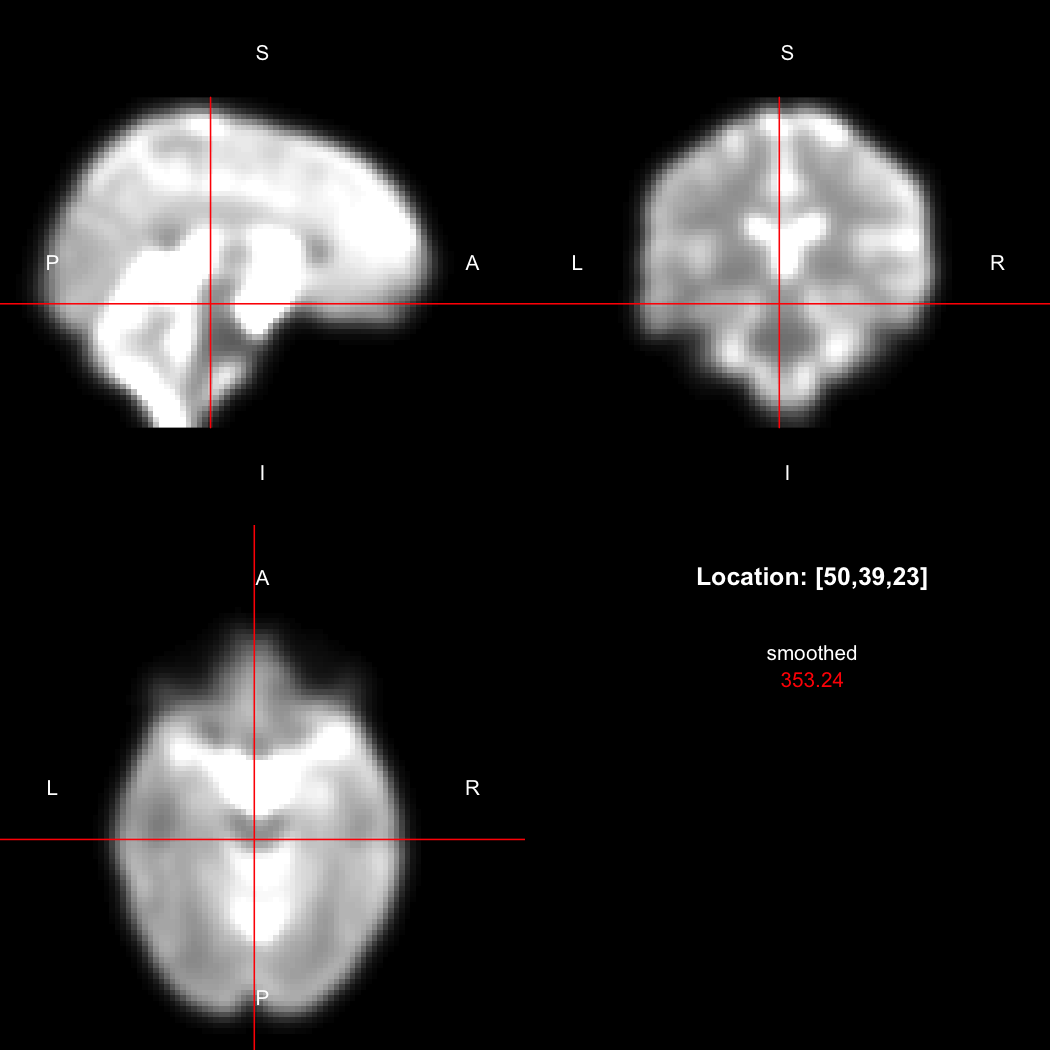

A simple example operation would be to smooth the image with a Gaussian smoothing kernel of standard deviation 4 mm. We can use standard R syntax to perform this operation, return a result, and then show it:

smoothed <- run(smooth_gauss(image, 4))

view(smoothed)

## Setting window to (0, 549.9)

plot of chunk standard

Here, smooth_gauss() requests the smoothing operation, and run() actually runs the pipeline and returns the processed image.